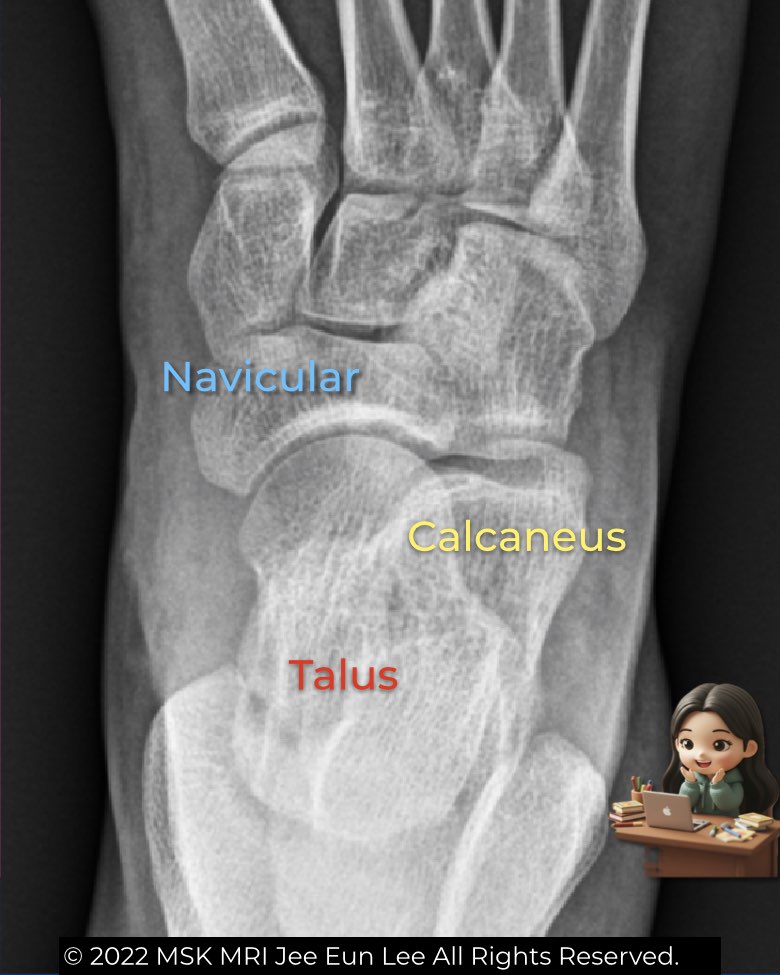

The AP and oblique foot views are essential for assessing alignment and detecting early coalitions.

- AP view: check the smooth alignment between the lateral margin of the talar head and the navicular. Any step-off suggests abnormality. The anterior process of the calcaneus is usually not seen. This view also allows angle measurements like the talar–first metatarsal angle to evaluate flatfoot.